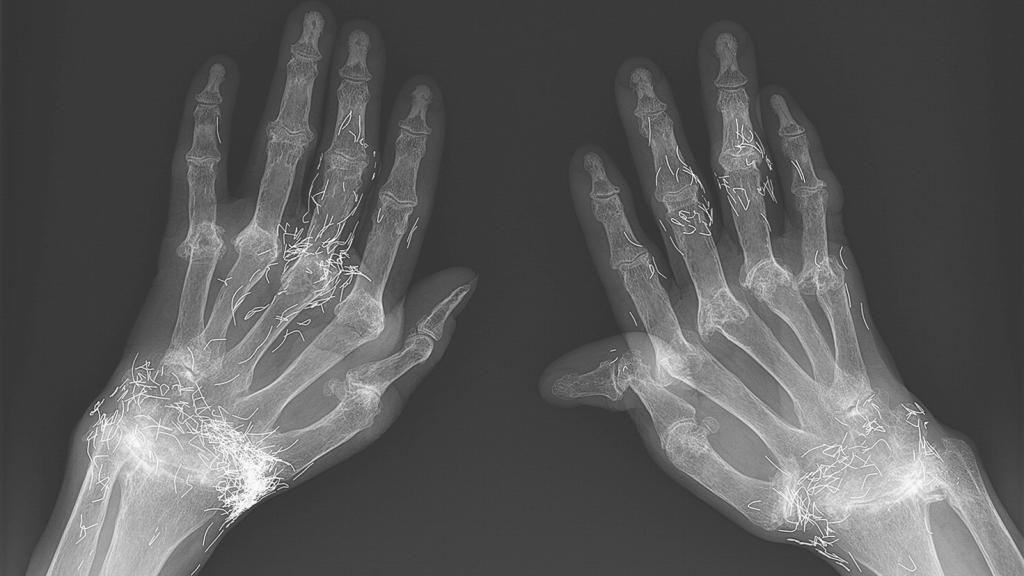

La radiografía de las manos de la mujer. New England Journal of Medicine

Como parte del estudio de su dolor, se le realizaron una serie de radiografías. Y es ahí dónde se manifestó el extraño hallazgo: filamentos de oro brillando en el interior de las muñecas y los dedos de la paciente. Y es que la mujer había recurrido a los remedios tradicionales antes de acudir a los médicos, con deplorables consecuencias.

Según refiere el informe de este caso, esta práctica usa mucho en la zona del este de Asia y en todo el mundo como forma de tratar el dolor articular. Sin embargo, el caso de esta mujer era llamativo por dos razones: la gravedad de su artritis reumatoide, la cual le causó deformidades a nivel de manos y pies; y el hecho de que los hilos de oro se insertaron en casi todas las articulaciones que tenía de formadas en sus manos.